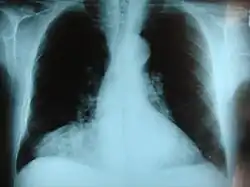

Morgagni hernia seen on a chest radiograph.